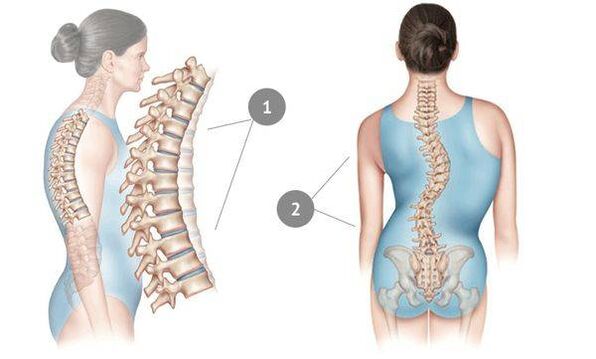

Грудны астэахандроз - захворванне, звычайна якое з'яўляецца ў дарослым узросце і доўга не праяўляе сябе ў поўнай меры.Абумоўлена гэта тым, што грудны аддзел хрыбетніка натуральнай выявай падтрымліваюць і фіксуюць рэбры - таму міжпазваночным дыскам забяспечваецца добрая абарона.

Ядро хрыбетнага дыска пры гэтай хваробе вытанчаецца і ўсыхае, фіброзная тканіна вакол яго пачынае разбурацца, храстковая тканіна падвяргаецца негатыўным зменам.Пазваночнік аказваецца няздольны спраўляцца са звычайнымі нагрузкамі - і выяўляецца гэта ў першую чаргу ў з'яўленні боляў, спачатку выяўленых невыразна, але з часам якія ўзмацняюцца ўсё больш.Аднак пры значных нагрузках - маларухомым ладзе жыцця, сядзячай працы, пастаянных стрэсах, дрэннай выправе і траўмах спіны - рана ці позна астэахандроз дзівіць грудны аддзел.Захворванне лічыцца вельмі распаўсюджаным - ад яго пакутуе кожны трэці дарослы чалавек.

Астэахандроз груднога аддзела пазваночніка не ўяўляе небяспекі непасрэдна для жыцця пацыента.Аднак у запушчаным стане ён можа прывесці да значных ускладненняў:

- з'яўленні хранічнай міжрэбернай неўралгіі;

- кілы груднога аддзела;

- здушванні спіннога мозгу ў пашкоджаным участку пазваночніка.

Запушчаны астэахандроз хрыбетніка выяўляецца ў скаліёзе, часам хвароба пераходзіць на шыйныя пазванкі і становіцца прычынай страты голасу.

Акрамя таго, моцнае паслабленне хрыбетніка ў грудным аддзеле можа прывесці да дэфармацыі ўнутраных органаў брушыны.У сваю чаргу, гэта з вялікай верагоднасцю пацягне за сабой разнастайныя засмучэнні стрававальнага гасцінца - страўніка, падстраўнікавай залозы, печані, нырак, жоўцевыводзячых шляхоў.